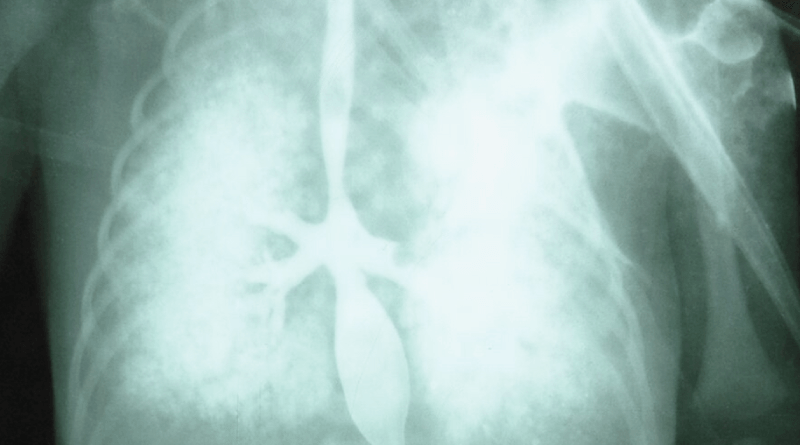

식도기관 누관 -신생아, 소스 : New egland Journal of medicine 3/6/2021

| 선천성 식도폐쇄와 기관식도 누관(선천성 식도 폐쇄증, 기관식도 루)의 진단 |

- 병력 증상 징후 진찰소견 등을 종합해서 이 병이 의심되면 흉부와 복부의 X선 사진검사, 흉부와 복부의 초음파 검사, 바륨 식도 X선 사진 검사, 기관 내시경, 식도와 위 내시경검사 등으로 진단할 수 있다.